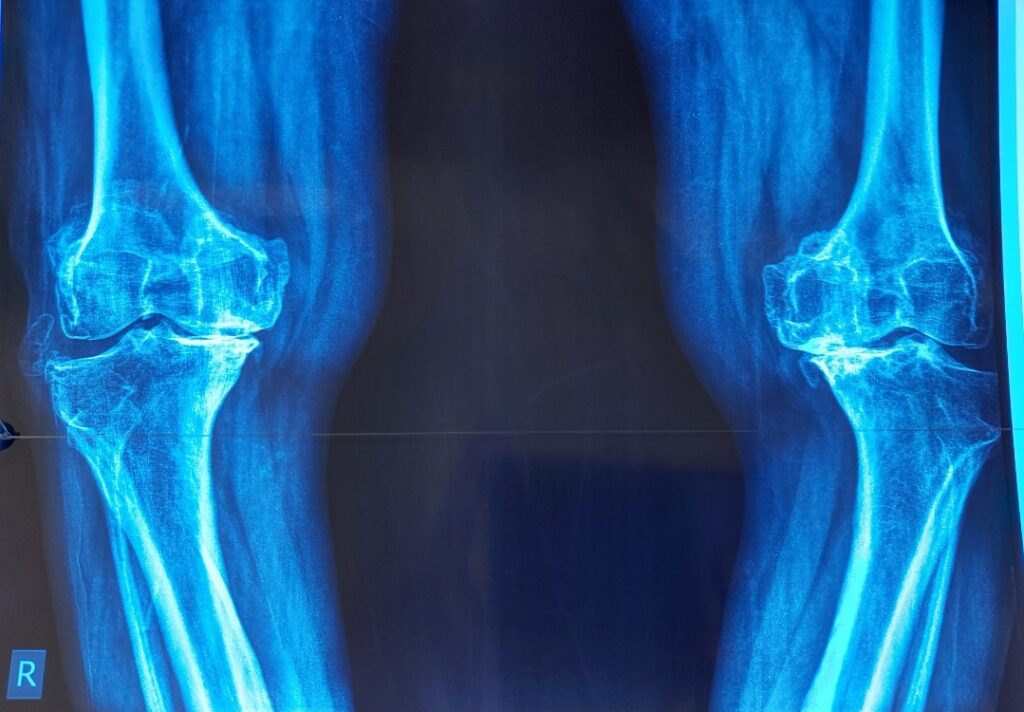

Total Knee Replacement or knee arthroplasty is a surgery in which doctors replace damaged tissues of the knee with artificial implants. This helps reduce pain and improve movement. In Pakistan, the methods include total and partial Knee Replacement. Only a few Orthopedic Doctors perform minimally invasive Knee Surgery. Dr. Imran Salim Malik is the top Orthopedic Surgeon in Lahore who performs total Knee Replacement using advanced minimally invasive procedures that not only reduce post surgical infection risks but also improves mobility.